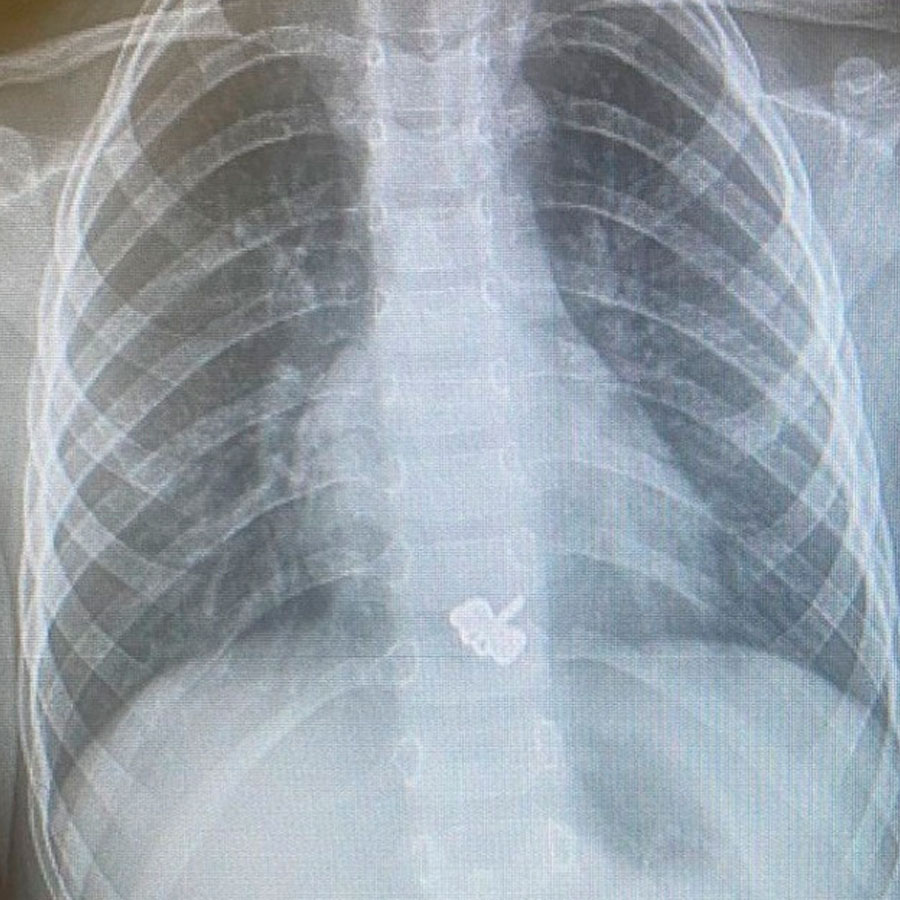

Вот вам загадка. Что объединяет все предметы на фото?

Правильно. Все их в разное время "вытищили" из маленьких пациентов в Башкирии.

Монеты, магнитные шарики, зубочистка, два гвоздя, игрушка из киндера, магнитная рыбка, наушники, заколка...иногда удивительно что может проглотить ребенок.